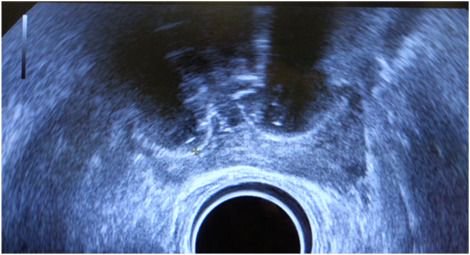

In 2018, @UCL research made significant advances in the diagnosis of prostate #cancer. Centre for Medical Imaging Prof Shonit Punwani (Shonit Punwani) discusses using MRI to better understand some of the most aggressive cancers. Read more here: bit.ly/2SGUK4r